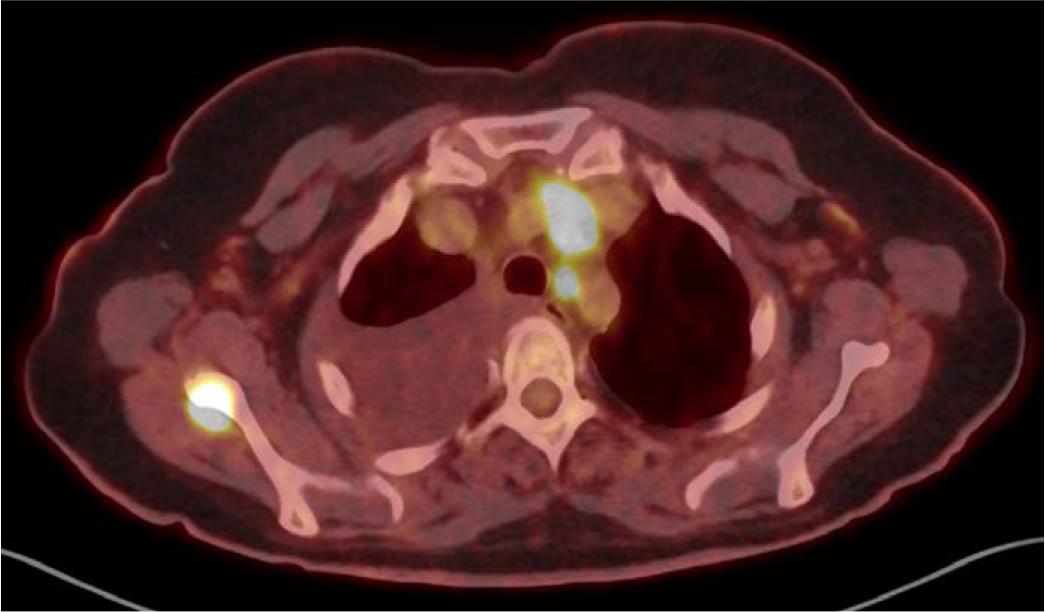

[18F]FDG PET/CT, axial plane – increased radiotracer uptake in the superior aortic recess, non-enlarged left upper paratracheal lymph node, and right scapula – with no corresponding lesions in the scapula in the contrast-enhanced CT performed later. Additionally, the non-contrast CT scan shows a large amount of fluid in the right pleural cavity.